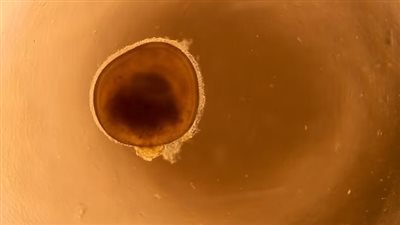

أخبره الأطباء أنه أصيب بعدوى بكتيرية خطيرة في عينه اليسرى، تسببت في إتلاف قرنيته تمامًا وتعتم عينه، بسبب نومه بالعدسات اللاصقة.

ويمتلك الأمريكي جروشين الآن 20% فقط من الرؤية في عينه اليسرى، على الرغم من أنه قادر على رؤية الضوء والألوان، في حين أنه قد لا يزال بحاجة إلى زرع القرنية، ويقول طبيبه إن حالته كان من الممكن أن تكون أسوأ بكثير.